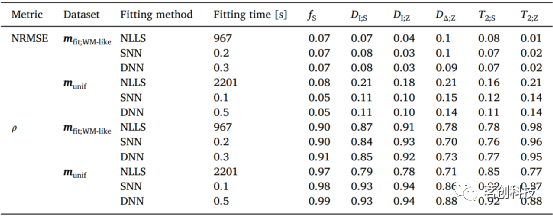

基于ANN估计的误差和预测-目标相关性汇总在表2中,其中还将它们与传统的NLLS求解器进行了比较。NLLS、SNN和DNN方法对于旨在捕获WM(T2,D)属性的silico数据集都具有相当的准确性。相比之下,对于合成的munif参数向量,函数拟合网络比NLLS方法更精确。

表2.基于DNN、SNN和NLLS拟合方法的精度。